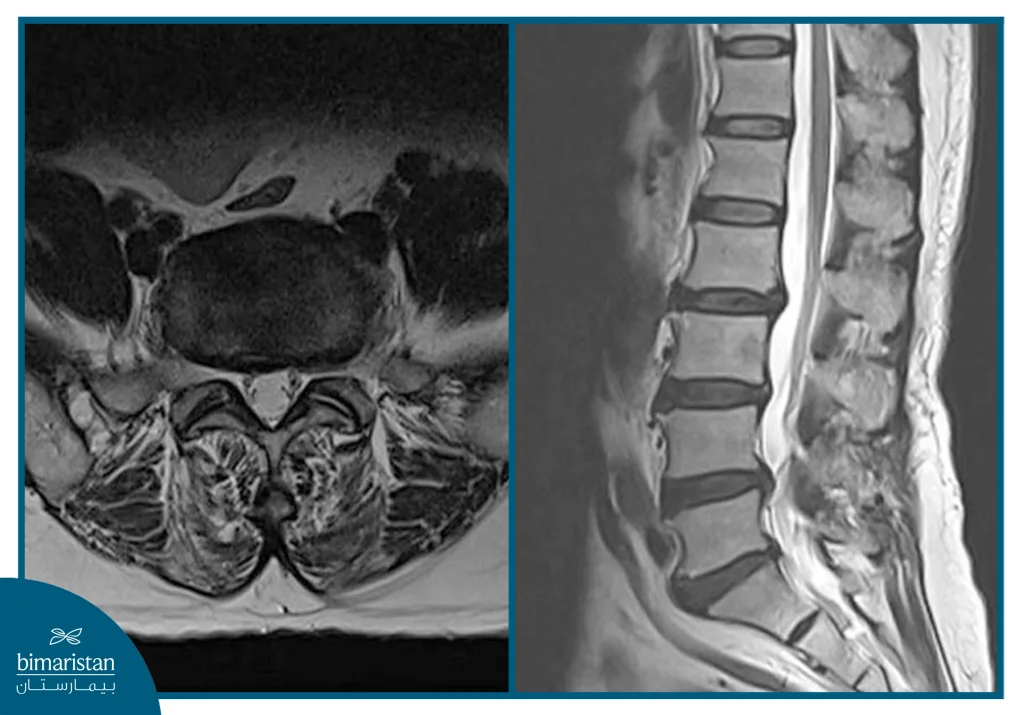

The meaning of herniated disc types by shape means according to what the magnetic resonance image (MRI) shows, as it shows fine details that allow the doctor to distinguish the types of discs in terms of the shape of the herniation and the degree of damage to the cartilage and adjacent nerves, and the herniated disc can be classified into three main forms that differ in terms of the severity of the condition and the appropriate treatment options.

Magnetic resonance imaging (MRI) is considered the most important means of diagnosing and differentiating between types of discs, as it shows the exact condition of the cartilage, the location of nerve compression, and the extent of damage to the surrounding tissues, but in some cases a CT scan or EMG may be required to help determine the degree of nerve irritation or rule out other diseases that may cause similar symptoms.